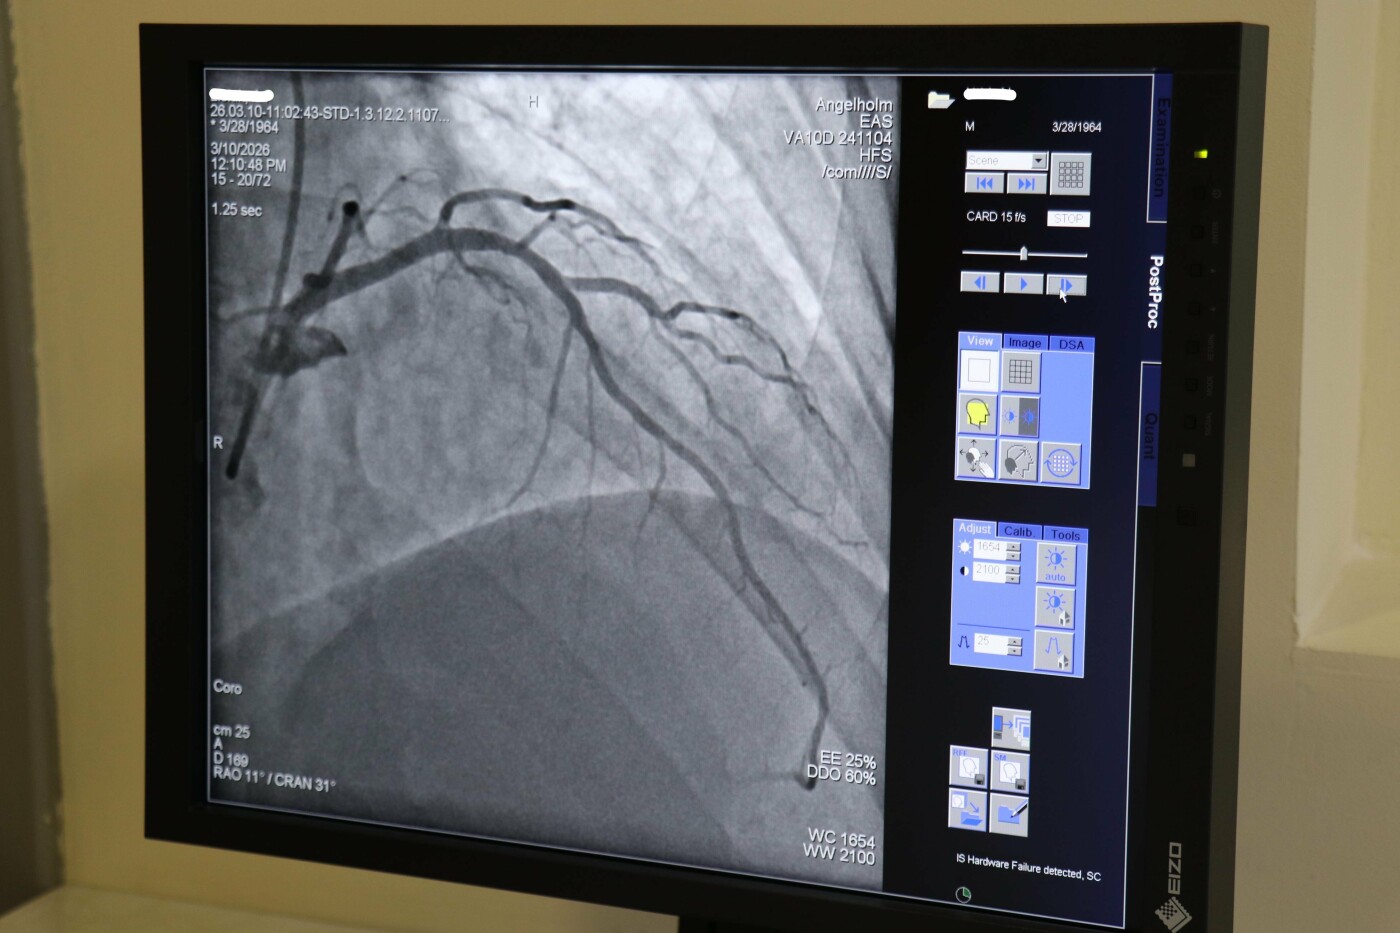

Коронарографія та стентування судин серця у медичному центрі Angelholm

У шведсько-медичному центрі Angelholm у Чернівцях виконують широкий спектр втручань у сфері інтервенційної кардіології та судинної хірургії. Однією з найпоширеніших процедур є коронарографія — дослідження судин серця, яке дозволяє виявити звуження або закупорку артерій, що можуть спричиняти ішемічну хворобу серця або інфаркт. Процедура проводиться 20-30 хвилин під місцевою анестезією. Тонкий катетер вводиться через артерію на руці, а у судини серця подається контрастна речовина, завдяки чому лікар бачить коронарні артерії та їх стан.

Якщо під час обстеження виявляють критичні звуження, лікар може виконати стентування коронарних артерій — встановлення спеціального металевого каркаса, який підтримує просвіт судини та відновлює кровопостачання серцевого м’яза. Процедура так само виконується за допомогою катетера, через який лікар вводить стент до місця звуження судини і розкриває його, що забезпечує повноцінний кровотік. Це ефективний спосіб профілактики інфаркту та лікування ішемічної хвороби серця.